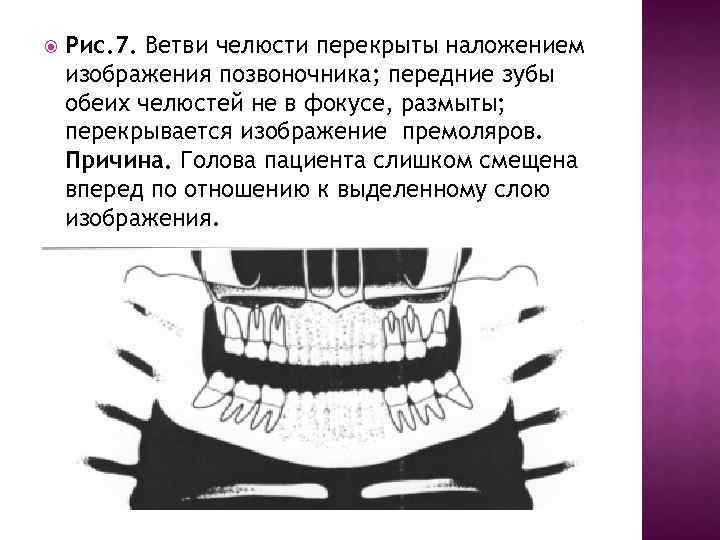

Рис. 7. Ветви челюсти перекрыты наложением изображения позвоночника; передние зубы обеих челюстей не в фокусе, размыты; перекрывается изображение премоляров. Причина. Голова пациента слишком смещена вперед по отношению к выделенному слою изображения.